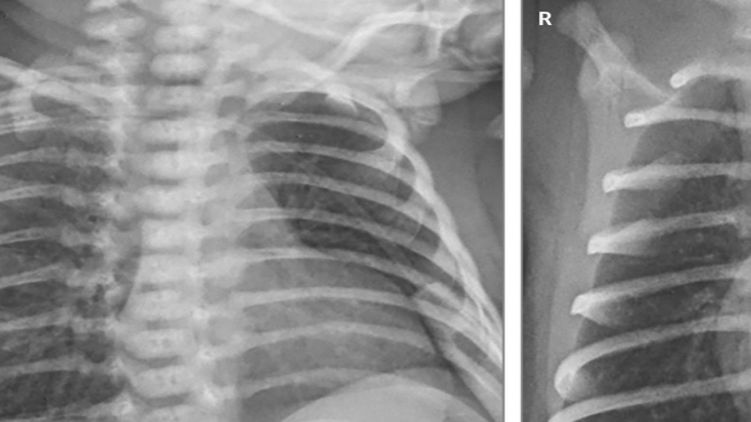

Коронавирус оказался опасным для новорожденных. Фото: Lingkong Zeng et al. / JAMA Pediatrics, 2020

Кроме пневмонии, у двоих маленьких пациентов проявилась лихорадка, а у недоношенного ребенка, который родился после 31 недели беременности, было подозрение на сепсис, который лечили антибиотиками. В отделении интенсивной терапии они провели 2, 4 и 11 дней (больше всего - недоношенный ребенок, ему также понадобилась искусственная вентиляция легких). Все остались живы.